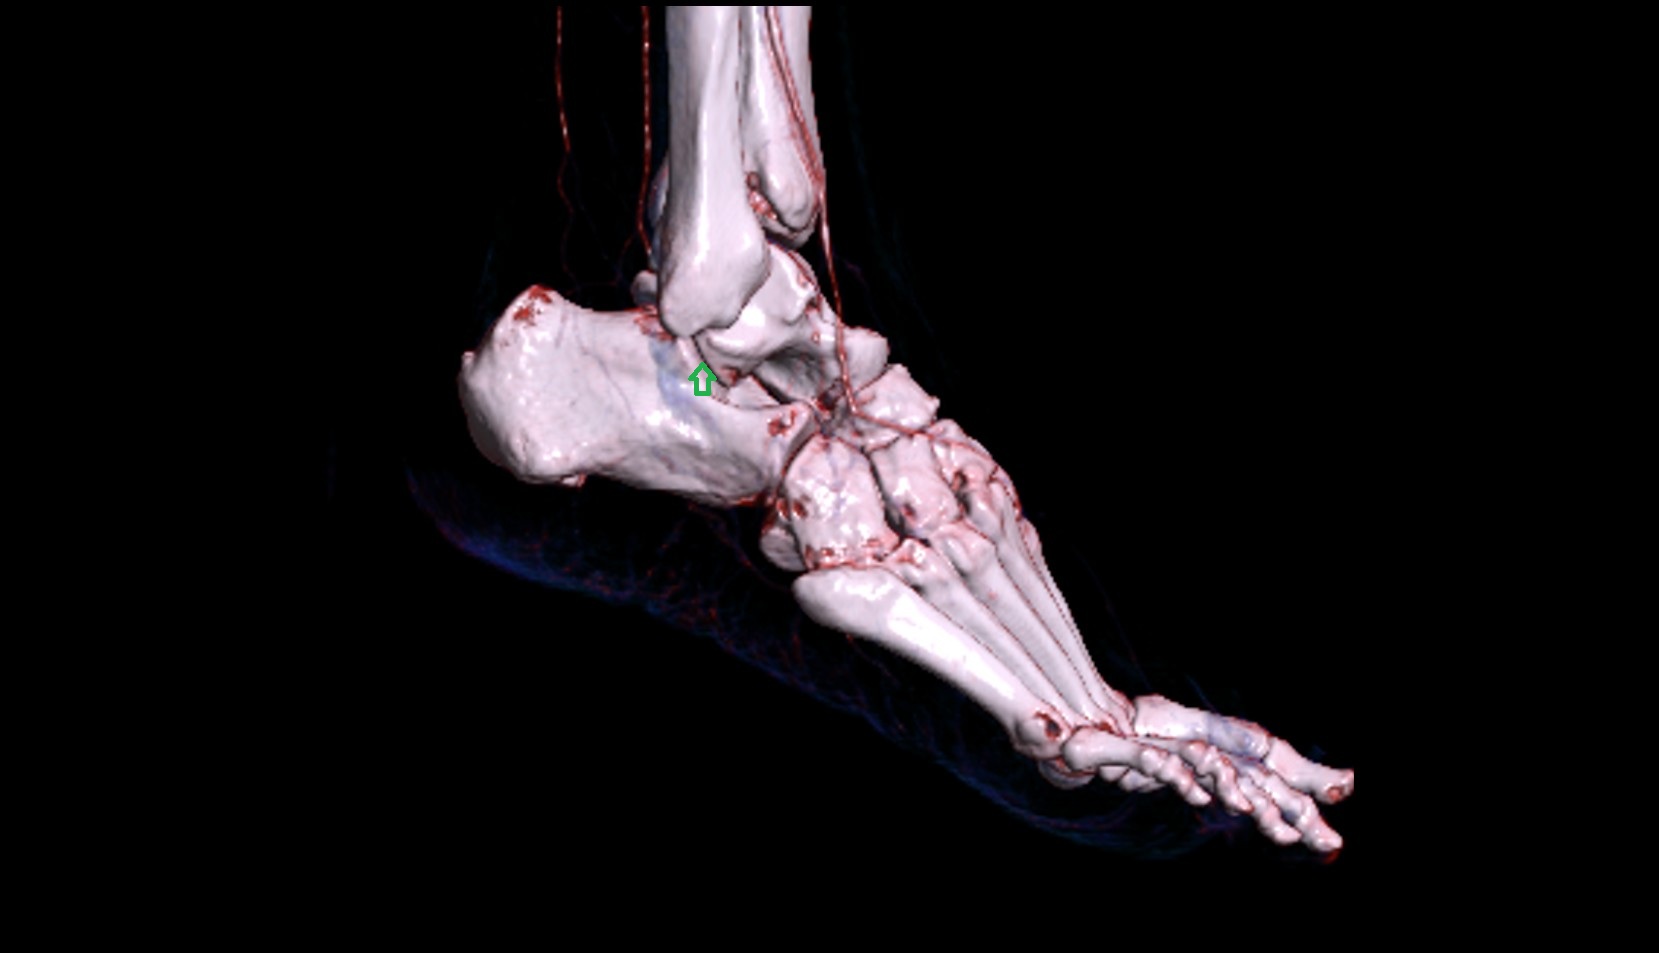

- Talus

- Head of talus

- Body of talus

- Neck of talus

- Calcaneus

- Medial malleolus

- Lateral malleolus

- Ankle joint

- Talocalcaneal joint